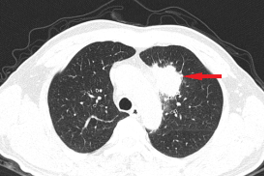

Anh C. được chuyển đến Trung tâm Y học hạt nhân và Ung bướu để thực hiện các xét nghiệm chuyên sâu. Kết quả chọc hút tế bào học từ tuyến giáp cho thấy nam bệnh nhân mắc ung thư biểu mô tuyến giáp thể nhú. Kết quả sinh thiết hạch cổ kết hợp nhuộm hóa mô miễn dịch tiếp tục phát hiện anh đồng thời mắc u lympho ác tính không Hodgkin dòng tế bào B lớn lan tỏa, giai đoạn III. Đây là trường hợp hiếm gặp khi bệnh nhân cùng lúc đối mặt với hai loại ung thư.

Trước tình trạng phức tạp, các bác sĩ quyết định ưu tiên điều trị u lympho ác tính không Hodgkin trước, do bệnh này tiến triển nhanh và nguy hiểm hơn.

Sau khi hoàn thành 6 chu kỳ hóa trị, anh C. được đánh giá đã đáp ứng hoàn toàn với điều trị u lympho. Tiếp đó, anh trải qua phẫu thuật cắt bỏ tuyến giáp, sử dụng I-131 và bổ sung hormone tuyến giáp thay thế để điều trị ung thư tuyến giáp thể nhú. Hiện tại, anh vẫn được theo dõi định kỳ để kiểm tra cả hai bệnh ung thư, đảm bảo không tái phát.